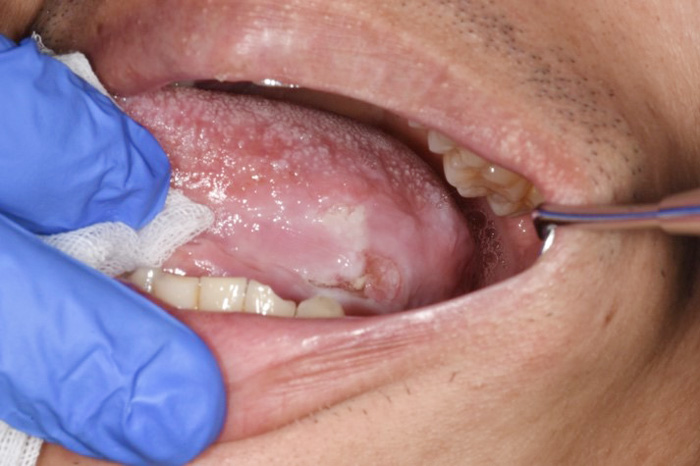

代表画像(舌がん)

舌がん

治療後(前腕皮弁で再建)

令和4年から口腔腫瘍科を新たに開設させていただきました。口腔腫瘍科で主に扱う疾患は口腔がん(舌がん、歯肉がん、頬粘膜がん、口蓋がん、口底がんなど)です。また、口腔潜在的悪性疾患としての前がん病変(白板症、紅板症など)や、前がん状態(口腔扁平苔癬)なども取り扱います。治療については手術療法、化学療法、放射線療法などを疾患により組み合わせて行います。広範囲にわたる手術などは関係各科と連携・協力し適切に進めていきます。